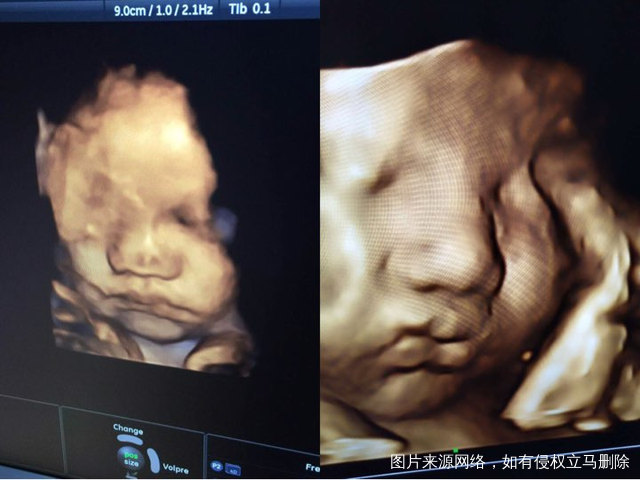

求助医生帮忙看看宝宝有没有下唇裂

每次B超都拍了宝宝的脸部,可最后一次拍照感觉下嘴唇样子怪怪的,不知道是不是唇裂还是影像拍摄问题,求医生帮忙看看,谢谢了!

左边是上一次拍的,右边是最近一次拍的